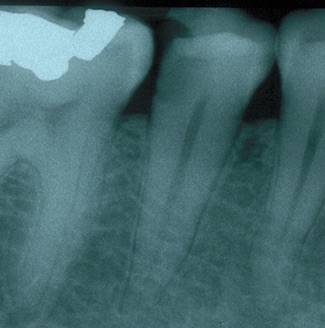

Fig 3. Determining a diagnosis with a radiograph only can lead the clinician to treat tooth No. 29 because of the distal decay. However, if the proper diagnostic tests are performed on tooth No. 29, it should reveal the pulp tested necrotic and it is tooth No. 30 that has a symptomatic irreversible pulpitis.

Figure 3

When a patient presents for restorative treatment and reports that a tooth is asymptomatic, a dentist may assume that the pulpal and periradicular diagnosis is within normal limits and hence may skip the above objective clinical tests, with the possible exception of taking a radiograph. However, using only a dental radiograph to determine the etiology of tooth pain and the pretreatment pulpal and periradicular status may lead to a pulpal and periradicular misdiagnosis (Figure 3). Therefore, a clinician must perform all five objective tests to obtain an accurate pretreatment pulpal and periradicular diagnosis.